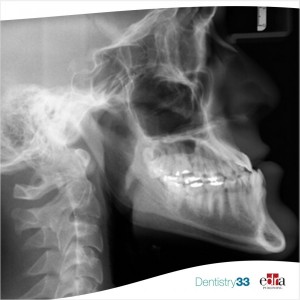

Orthodontics 31 March 2023

Video: Dr. David Sarver passes the torch to the next generation of orthodontists

Dr. David Sarver talked about his background in dentistry and how he manages his well-established practice. He also talked about his upcoming book.